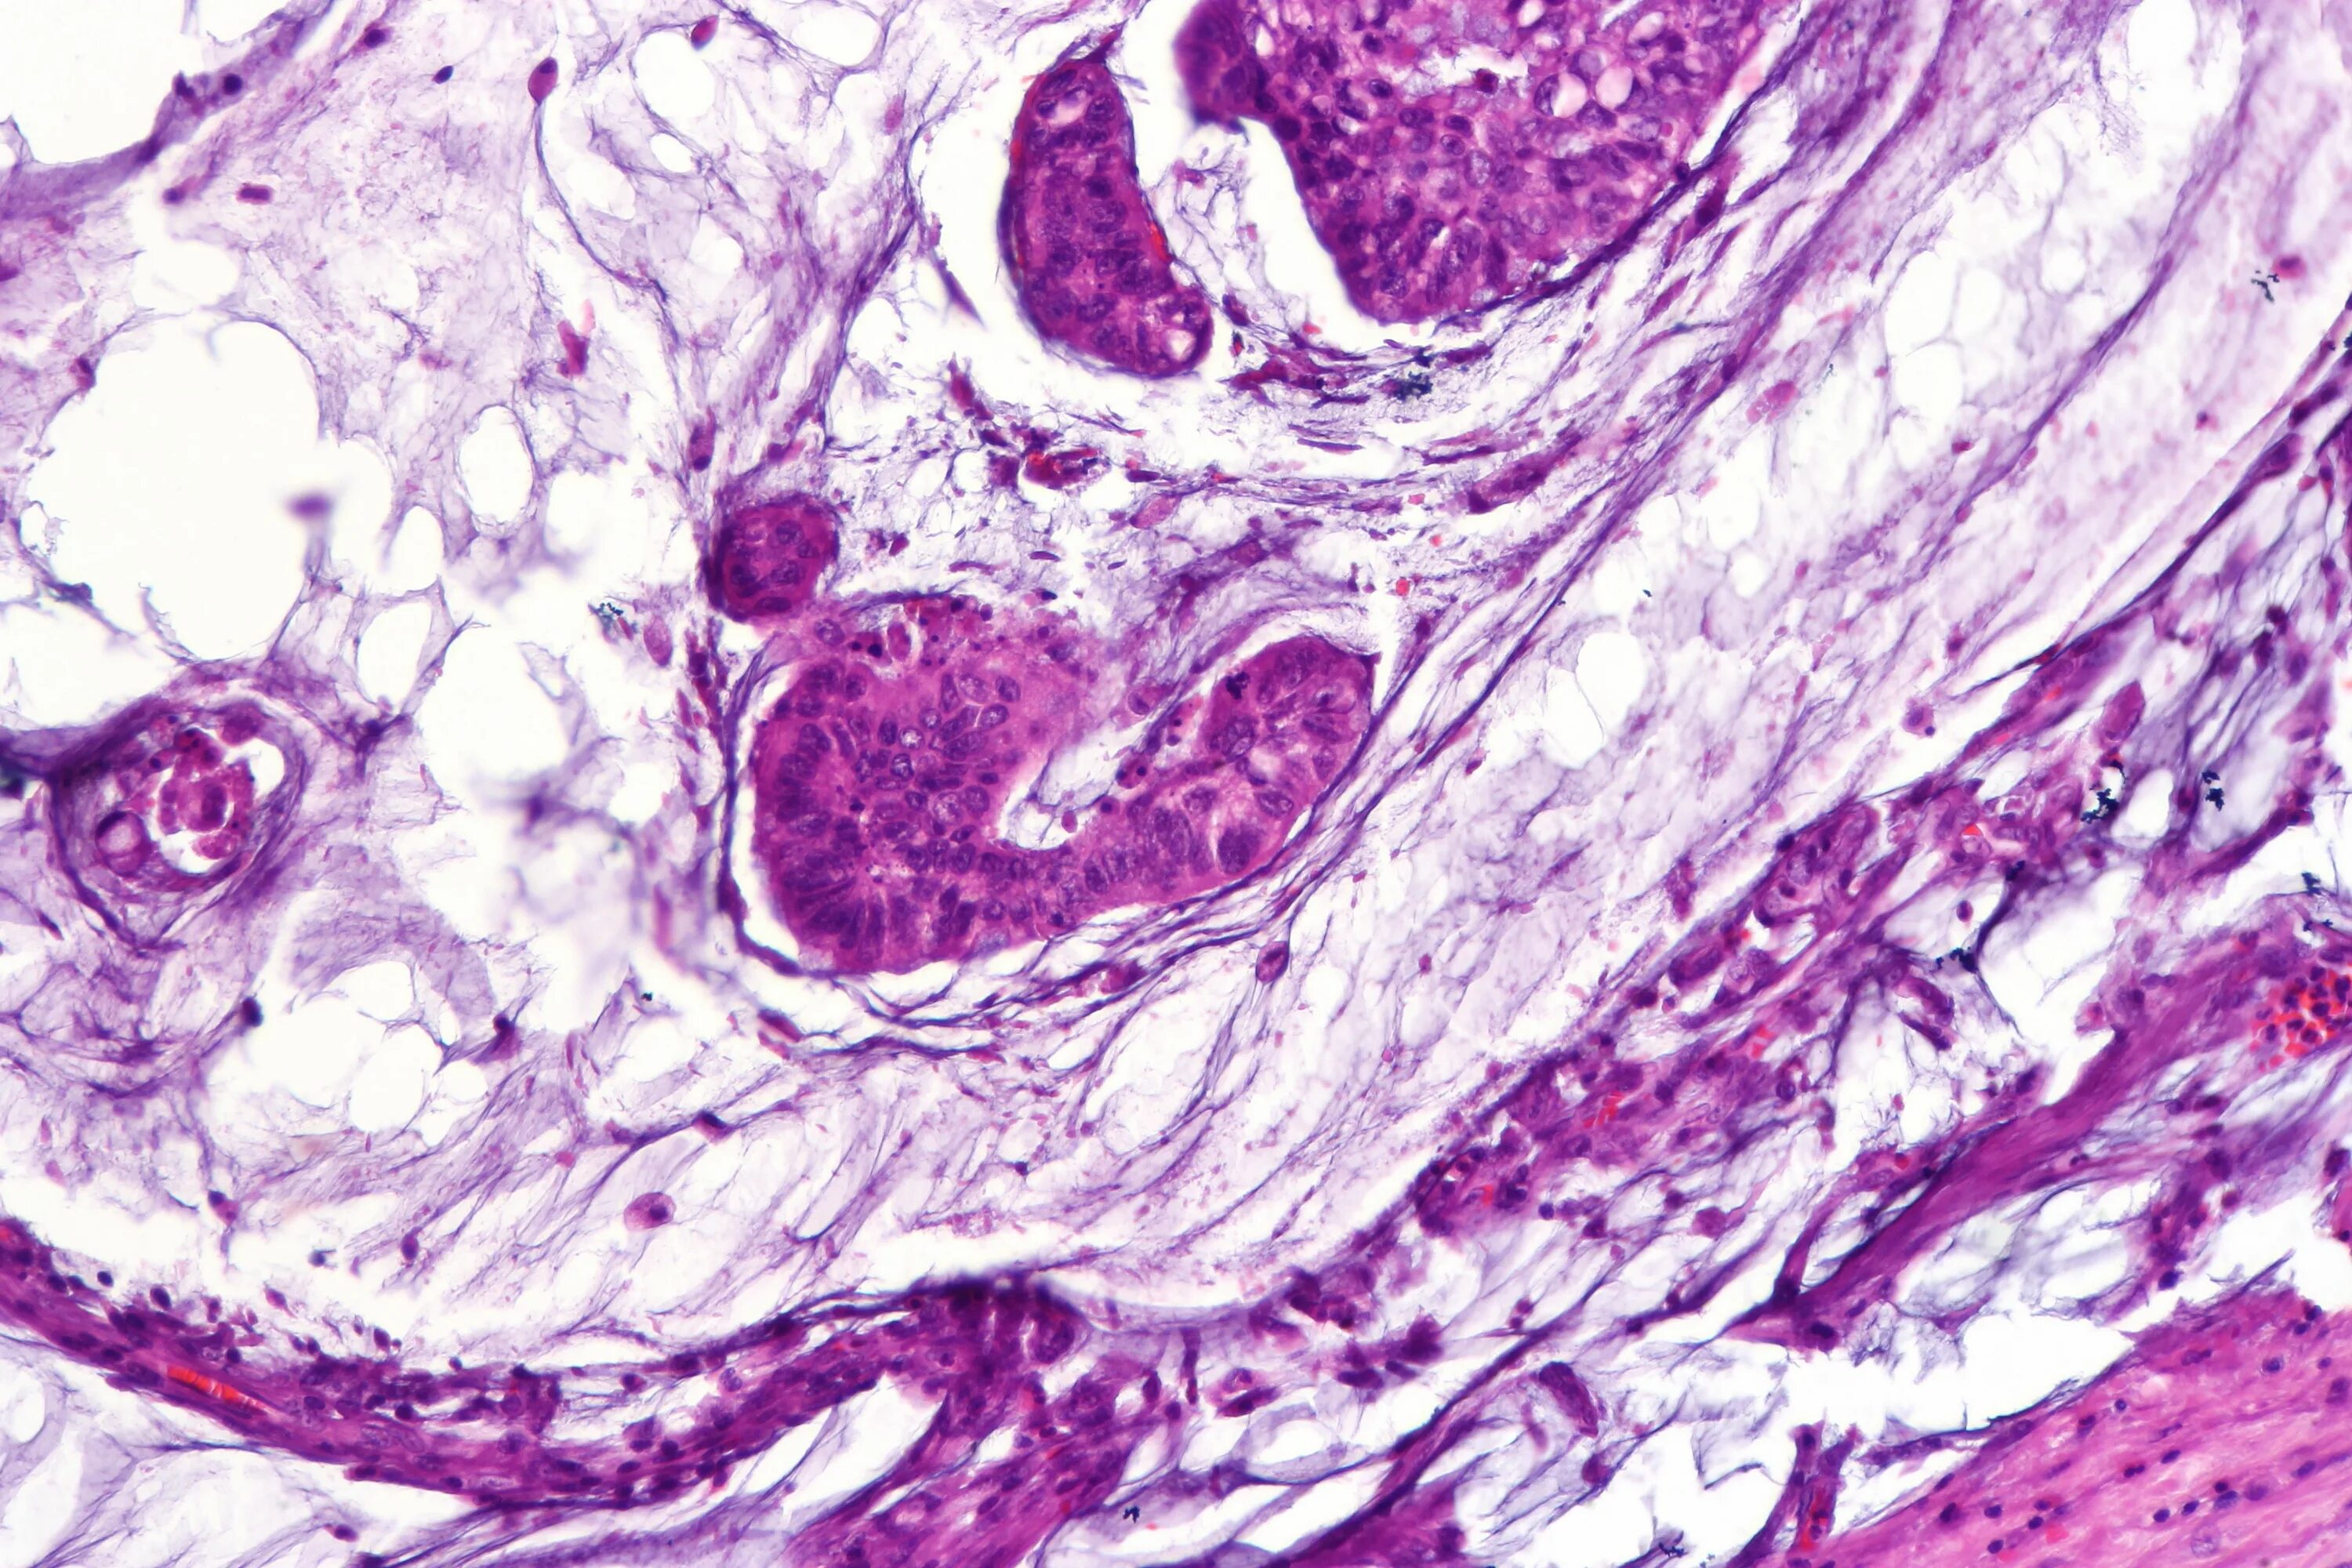

Гистология аденокарциномы